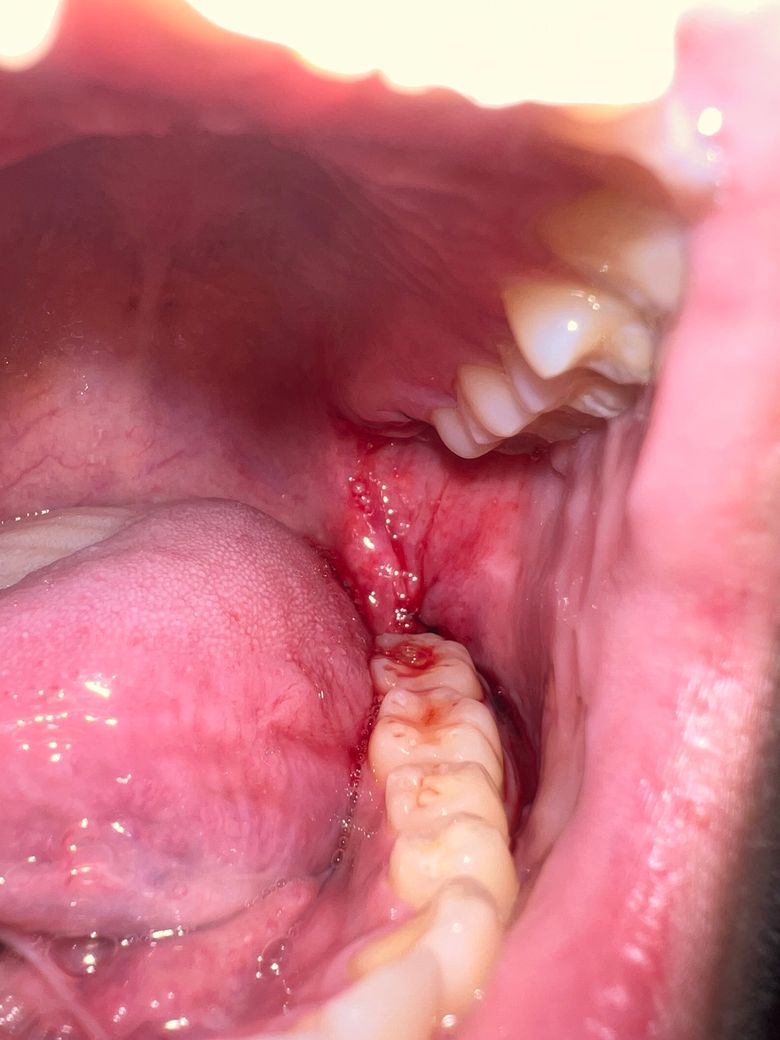

사랑니 발치했는데 이 정도면 지혈된건가요?

이번 사랑니는 지혈이 오랜시간 잘 안됐는데 이정도면 수면에는 문제 없을까요? 상악, 하악 매복 발치했고 거즈만 한 8시간 가까이 교체하면서 물었는데 뺀지는 1시간 정도 지났습니다

• 1번 째 사진

수면에는 문제 없을 것으로 판단되며 미세하게 피가 새어나오는 정도는 문제 되진 않습니다.

사진상으로 보면 아직 확실히 지혈이 된건 아니니 거즈를 좀더 꽉 깨물고 계시는게 좋을것같습니다.

사진으로 봤을 경우에는 지혈이 된 것으로 보입니다. 사랑니를 발치한 부위를 입을 크게 벌려 확인을 하거나 하는 행위는 발치한 부위를 자극하게 하여 출혈이 지속될 수 있습니다. 사랑니를 발치한 부위가 자극되지 않도록 하는 것이 좋습니다.